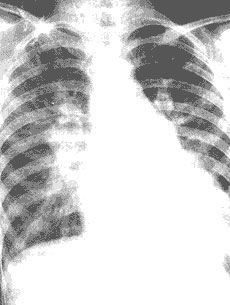

胸部X线检查 示心影增大 早期为左心室增大 晚期时右心室亦增大 分流量较多者左心房亦扩大 升主动脉和主动脉弓阴影增宽 肺动脉段突出 肺动脉分支增粗 肺野充血(图8) 有时透视下可见肺门“舞蹈”征

图8 动脉导管未闭病人胸部X线摄片

(1)后前位胸片示两肺充血 心影扩大 尤以左心室增大为甚 主动脉结增宽 肺总动脉扩大膨出 (2)左前斜位胸片示左心室明显增大 左心房 右心室也增大